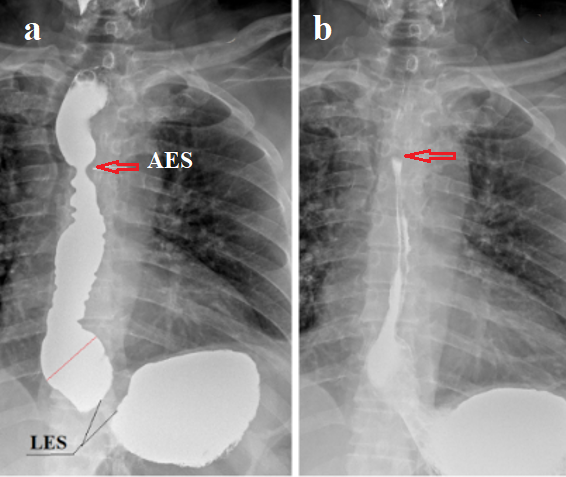

By applying abdominal compression during barium swallow, I found contraction of the LES, which is the non-contrast space located between esophagus and stomach contrasted with barium (Figure 1.a). I measured its length in people of different ages who had recently developed gastroesophageal problems. Since the measurement results were completely consistent with the results of manometric measurements, I believe that they are close to the true norm [6]. In adults, the length of the LES was in the range of 3.2-4.2 cm (3.60±0.08 cm) [7]. In patients with GERD, the length of the LES was shorter than the minimal limit of norm and depended on the degree of damage to the LES, the strength and duration of the provocation (the magnitude of gastric pressure). These findings were completely consistent with manometric [8] and histological studies [9], indicating a shortening of the LES in GERD due to the opening of its intra-abdominal part (Figure 1 b-e).

Figure 1. Radiographs of the esophagogastric junction in patients GERD with abdominal compression during barium intake. (a). A gap without contrast is seen between the esophagus and stomach due to contraction of the LES in response to increased pressure in the stomach. Longitudinal folds in the LES and esophagus indicate esophagitis. (b-c). After filling the stomach with barium (b). During the water-siphon test, barium refluxed into the esophagus due to wide opening of the intra-abdominal portion of the LES – angular deformation above the red line (c). (d). Study of the patient before and (e) during abdominal compression. Abdominal compression caused a sharp shortening of the LES with angular deformation of the image because of opening of the intra-abdominal portion of the LES.